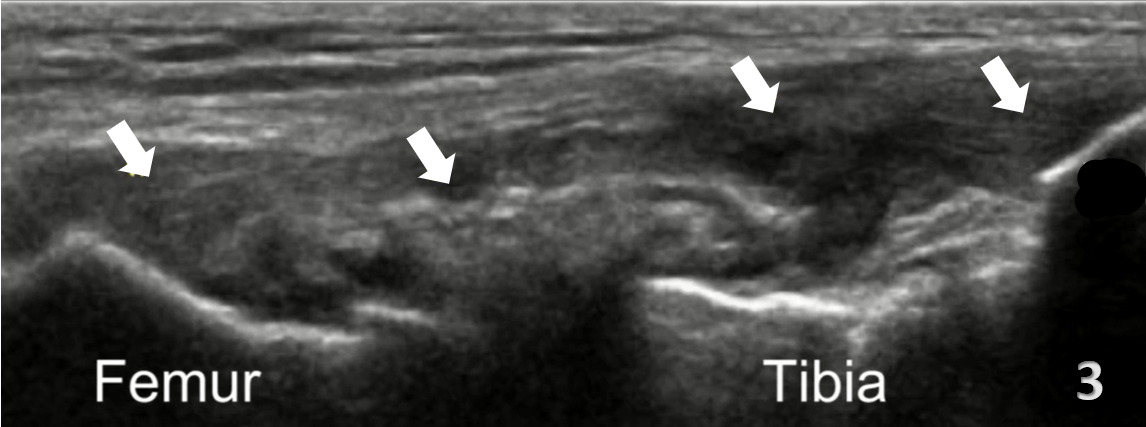

Pathologic Findings in Lateral Collateral Ligament Injury

Disruption of fibrillar pattern of the ligament in partial tears and ruptures.

Associated joint effusion, presenting as anechoic regions.

Calcifications near the enthesis sites.